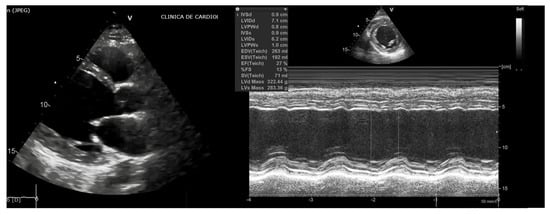

2. Case Report